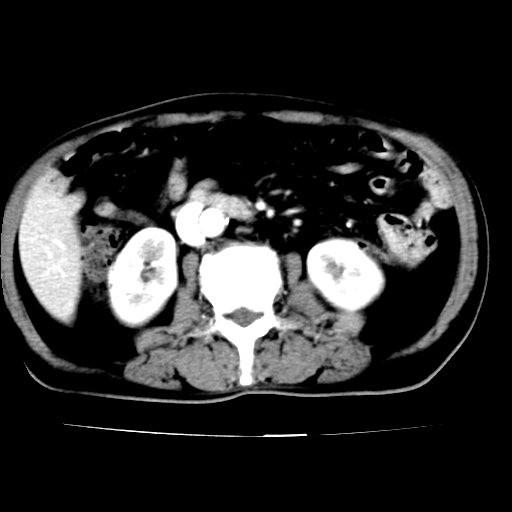

男,75岁,腹痛月余,彩超发现脐周腹主动脉异常回声。临床诊断:腹主动脉瘤。

ct诊断:右骼总动脉囊性动脉瘤并瘤内附壁血栓形成,与下腔静脉之间形成动静脉瘘。

请问各位老师:能排除动脉瘤破裂的可能吗?

各位老师注意到下腔静脉的充盈缺损了吗?注意到动静脉漏了吗?

当时是扫描的标准动脉期,可是下腔静脉与腹主动脉同步强化且幅度一致。所以我想动静脉瘘是存在的。